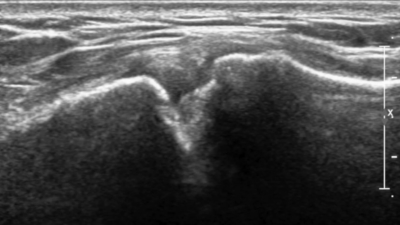

Echografisch onderzoek van het AC gewricht: de echokop wordt boven op de schouder geplaatst ter hoogte van het sleutelbeen om het gewricht in beeld te brengen

Wat zien we op een echo?

Met echo kunnen we de weke delen van het AC gewricht goed in beeld brengen.

We beoordelen het gewrichtskapsel, de gewrichtsbanden en de bovenkant van het gewricht waar vaak botwoekeringen ontstaan. Ook kunnen we zien of er sprake is van vocht of een ontsteking in het gewricht.

Maar de echo vertelt meer dan alleen het AC gewricht. Tijdens hetzelfde onderzoek bekijken we ook de structuren eronder: de schouderpezen en de slijmbeurs.

Echo AC gewricht Artrose

We kunnen ook beide schouders vergelijken. Is het AC gewricht aan de pijnlijke kant duidelijk dikker of meer ontstoken dan aan de andere kant? Dan is dat een sterke aanwijzing.

Regelmatig zien we een gemengd beeld: AC gewricht klachten in combinatie met een slijmbeurs- of peesontsteking. De echo helpt ons om te onderscheiden wat er allemaal speelt.

⚠️ Let op: Of botwoekeringen aan de onderkant van het AC gewricht druk geven op de rotator cuff is op een echo niet te beoordelen. Daarvoor is een röntgenfoto nodig.